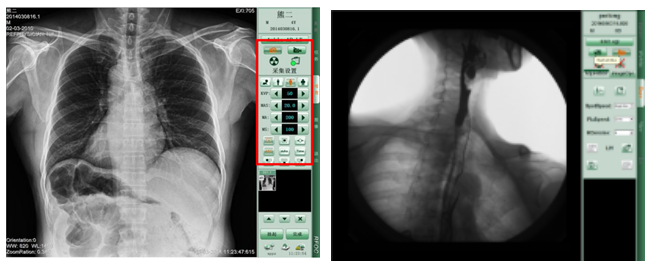

動態dr的高效、精準的診斷優勢獲得了很多醫院的青睞,而且多科室的臨床應用也越來越多,隨著國內廠家根據臨床應用的反饋結果,對動態dr的功能進行改善,動態dr越來越受到大家的歡迎,市場的發展前景也很大,并且動態dr具備數字拍片、數字透視、數字胃腸造影、可視化點片等功能,采購了一臺動態dr,等于擁有一個放射科,可以省機房、省人員、省預算、省使用成本。那么,國內生產動態dr的哪個生產廠家好呢?

PLD7600平板動態DR拍片效果-普愛醫療